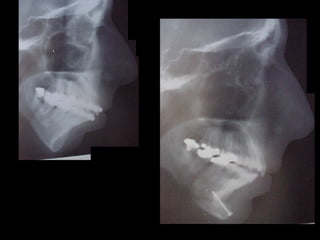

Antes (arriba) Después (derecha)

Radiografía

Lateral